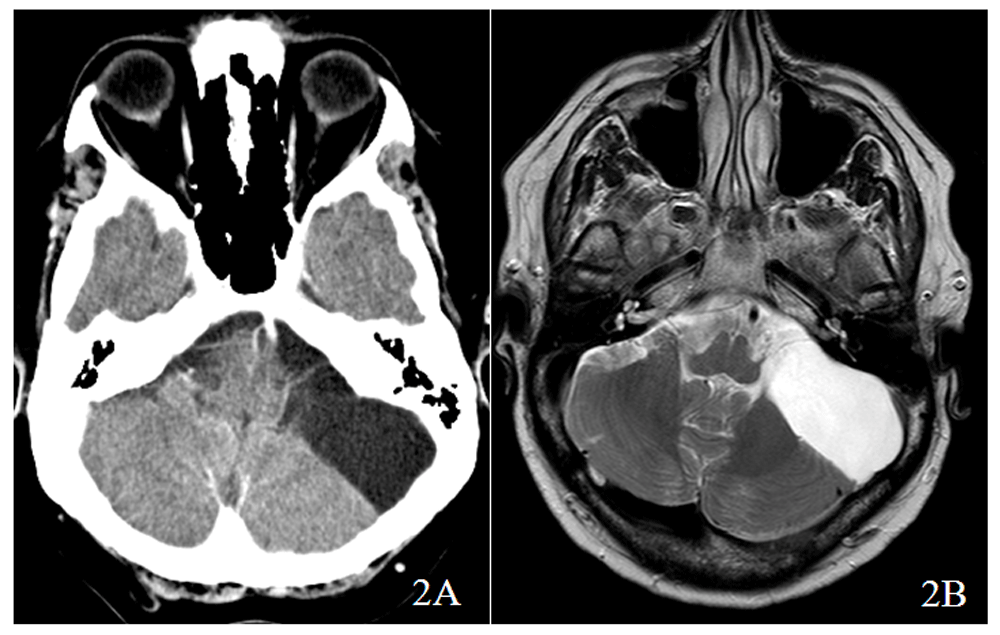

A head computed tomography (CT) scan showed the pre-existing cystic lesion in the left cerebellopontine angle with a slight right brainstem deviation, without associated edema (Figure 2A), confirmed by magnetic resonance imaging (Figure 2B). The case was discussed with the Neurosurgery Department and a lumbar puncture was postponed as it was considered a high-risk procedure. The patient started antibiotics with ceftriaxone (2 g q12h) and ampicillin. (2g q4h) At day 4, blood cultures came back positive for Cryptococcus neoformans sensitive to Posaconazole, Amphotericin B and Itraconazole, so that patient started Liposomal Amphotericin B (3mg/kg id) and Flucytosine (100 mg/kg per day orally in four divided doses) for 14 days and low dose corticotherapy (4 mg per day). There was a progressive improvement of the symptoms and patient was discharged after 19 days with prescription of Fluconazole (400mg per day).

Head computed tomography (CT) scan showed the pre-existing cystic lesion in the left cerebellopontine angle with a slight right brainstem deviation, without associated edema (2A), as confirmed by magnetic resonance imagining (MRI) (2B).